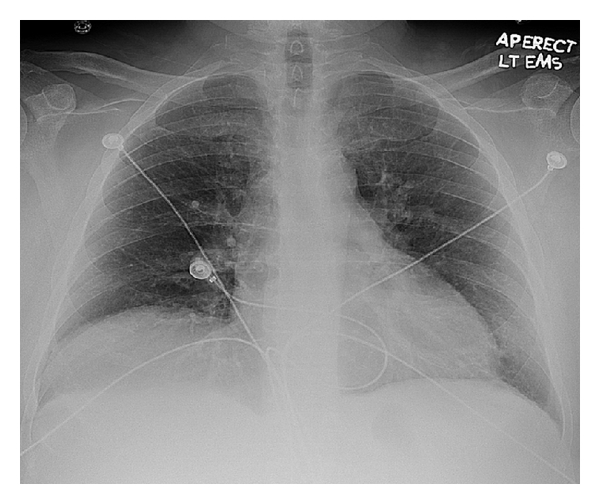

A 62-year-old male with a past history of COPD, hepatitis C infection, end-stage liver disease (MELD score 15), esophageal varices, and diabetes mellitus type II was admitted for progressive shortness of breath of one-week duration. Exam was notable for normothermia, heart rate 95 bpm, respirations 21 bpm, blood pressure 134/78, and oxygen saturation of 85% on RA; cardiopulmonary exam was remarkable for regular rate and rhythm, no murmurs, JVD 3 cm at 30 degree angle, nonpalpable PMI or right ventricular lift; lung exam showed diffuse expiratory wheezing without crackles or rhonchi. The remainder of the examination was unremarkable, including strong peripheral pulses and no edema or cyanosis. Chest X-ray showed no changes of hyperinflation or parenchymal infiltrates, small bilateral pleural effusions, and right hemidiaphragm elevation (Figure 1). Arterial blood gas showed a pH of 7.45, PaCO2 of 35.9 mm Hg, and PaO2 of 59 mm Hg. The respiratory alkalosis and A-a gradient raised concerns for venous thromboembolism (VTE), but lower extremity ultrasound was negative for thrombus. CT angiography was not performed due to renal dysfunction (Cr 4.7 mg/dL). A ventilation/perfusion scan showed low probability for VTE (Figure 2). On the second hospital day, he developed progressive hypotension and syncope in conjunction with worsened hypoxemia. A computed tomography of the head was negative for acute CVA or subdural hematoma. Echocardiography revealed a D-shaped left ventricle with normal systolic function, LVEF 65% (Figure 3). The right ventricle was moderately enlarged with decreased systolic function, but no tricuspid valve dysfunction. Over the subsequent 24 hours, the patient developed severe hypotension unresponsive to fluid resuscitation. Dobutamine therapy was instituted. Repeat echocardiography revealed a small left ventricular cavity (LVEF 50%) with progressive dilation and hypokinesis of the right ventricle and severe tricuspid regurgitation. Supportive measures including mechanical ventilation, vasopressors, and renal replacement therapy were instituted, but refractory shock persisted. The patient developed asystolic arrest. Further resuscitation was withheld in accordance with his family’s wishes and the patient expired 72 hrs after admission. Postmortem examination revealed moderately differentiated hepatocellular carcinoma (HCC) with involvement of all liver segments and innumerable tumor micronodules similar in size to the cirrhotic nodules but no dominant HCC lesion. There was invasion of the perihepatic vasculature including the portal vein. There were focal intravascular HCC tumor emboli to the right and left heart ventricles. Although no gross pulmonary emboli were seen, numerous small vessel and lymphatic metastatic HCC tumor microemboli involved all lung lobes (Figures 4, 5, and 6).